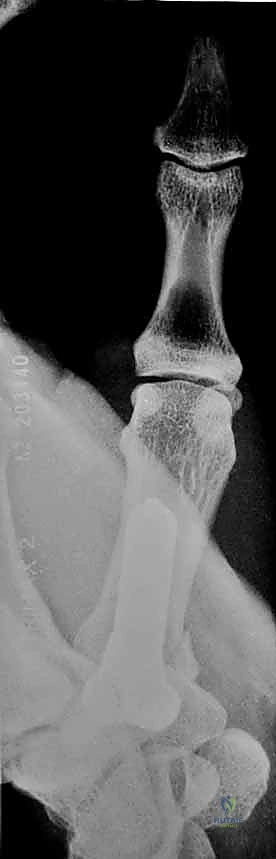

هو أشهر أنواع كسور قاعدة الإبهام وأكثرها تعقيداً. وهو كسر داخل المفصل يتميز بوجود خط كسر مائل يفصل شظية صغيرة من الجانب الراحي الزندي (Volar-Ulnar) لقاعدة المشط الأول.

* الديناميكا المرضية: المشكلة الكبرى في كسر بينيت هي "القوى العضلية المعاكسة". بينما تظل الشظية الصغيرة ثابتة في مكانها بفضل رباط المنقار القوي، تقوم عضلة "مبعدة الإبهام الطويلة" (Abductor Pollicis Longus - APL) بسحب الجزء الأكبر المتبقي من عظم المشط إلى الأعلى والخلف، مما يؤدي إلى خلع جزئي (Subluxation) للمفصل.

* هذا الكسر غير مستقر بطبيعته ويحتاج دائماً إلى تدخل لتثبيته.

2. التصوير بالأشعة السينية (X-rays)

هي الأداة التشخيصية الأولى والأهم. يتم إجراء صور أشعة بزوايا محددة جداً:

* المنظور الأمامي الخلفي (AP View).

* المنظور الجانبي الحقيقي (True Lateral View): وهو ضروري جداً لتقييم مدى الخلع أو الانزياح في المفصل.

* منظور روبرت (Robert's View): وضعية خاصة للأشعة السينية تظهر مفصل الإبهام الرسغي السنعي بوضوح تام وتكشف عن أدق التفاصيل في كسور بينيت ورولاندو.